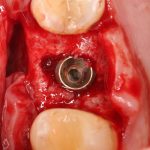

Через 3 месяца — вторая операция — установка имплантата в сформированный объем костной ткани:

Как видите. восстанавливается всё очень легко, никаких дефектов не остаётся, но при этом мы получаем важное преимущество: достаточную свободу движений при формировании субантральной полости и хороший визуальный контроль за состоянием слизистой оболочки. Никакая нажопная оптика или суперпупермикроскоп, к сожалению, не обеспечат подобный контроль при закрытом синуслифтинге. Да, операция получается травматичнее и масштабнее, чем «закрытый» синуслифтинг, но несёт в себе гораздо меньше рисков.